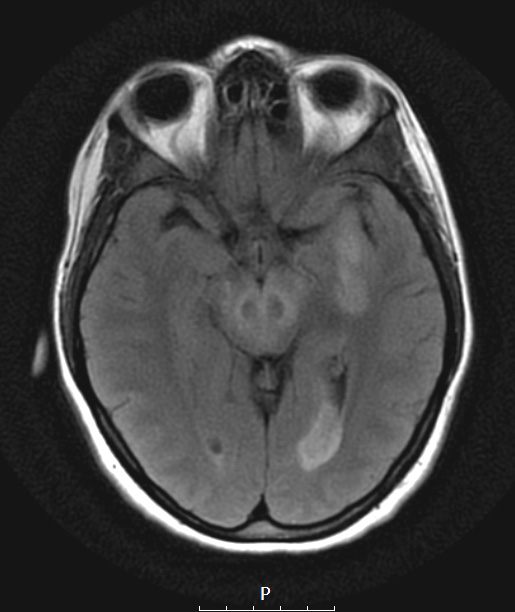

A T2 FLAIR scan shows multiple lesions in the subcortical and periventricular hemispheric regions and the brainstem.